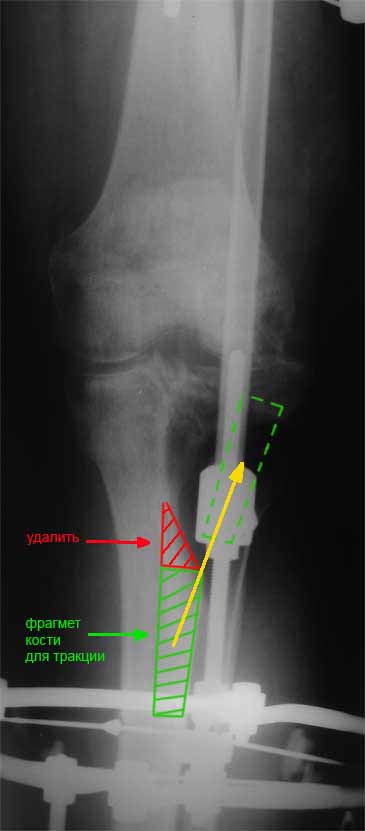

Я бы сделал пластику мягких тканей (торакодорзальный лоскут совместно с микрохирургами или пластику латеральной головкой икроножной мышцы) и выполнил бы краевой отщеп большеберцовой кости для его дистракции аппаратом в проксимальном направлении (рис. 1 – пример применения отщепа (авторство не мое), рис. 2 – схема предлагаемого варианта замещения дефекта кости).

Малоберцовую кость я бы пока не трогал. Она сослужит хорошую службу при начале нагрузки на ногу - будет служить дополнительным стабилизирующим и элементом.